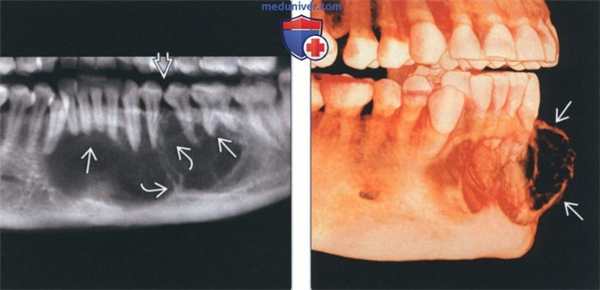

(Слева) На кадрированной панорамной реформатированной КЛКТ у женщины 30 лет определяется многокамерное образование значительных размеров, приводящее к наружной резорбции корней и смещению зубов. В образовании присутствуют множественные толстые трабекулы, некоторые из которых располагаются под практически прямыми углами.

(Справа) На КЛКТ (объемный рендеринг) у этой же пациентки определяется выраженное вздутие костей с лицевой стороны с наличием множественных толстых трабекул в структуре. Также определяется наружная резорбция корней передних зубов.